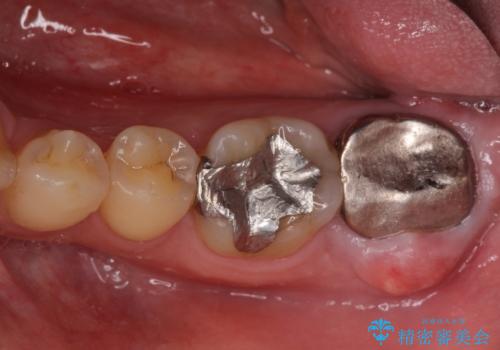

[20代男性] インプラント 失った歯の治療